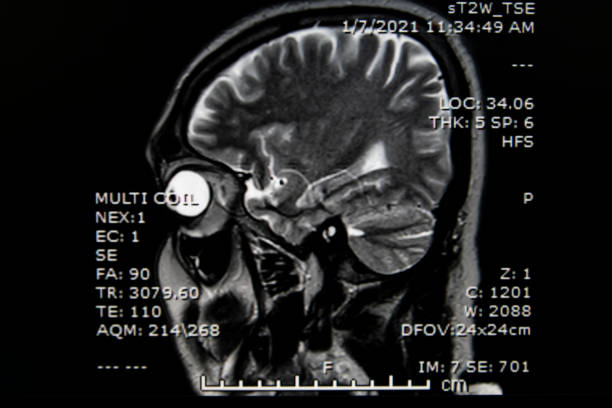

뇌경색은 뇌로 가는 혈류가 차단되면서 뇌세포가 손상되는 치명적인 질환으로, 전 세계적으로 주요 사망 원인 중 하나로 꼽힙니다. 특히 한국에서는 고령화와 서구화된 식습관, 그리고 스트레스가 뇌경색의 주요 위험 요소로 작용하고 있습니다. 뇌경색은 조기 발견과 빠른 치료가 이루어지지 않을 경우 심각한 후유증을 남길 수 있으며, 생명을 위협할 수 있습니다.

뇌경색의 발병을 막기 위해서는 전조증상을 인지하고, 신속한 치료와 더불어 재발 방지에 힘쓰는 것이 중요합니다. 이번 글에서는 뇌경색의 전조증상, 치료 방법, 재발 확률, 그리고 원인에 대해 심층적으로 살펴보겠습니다.